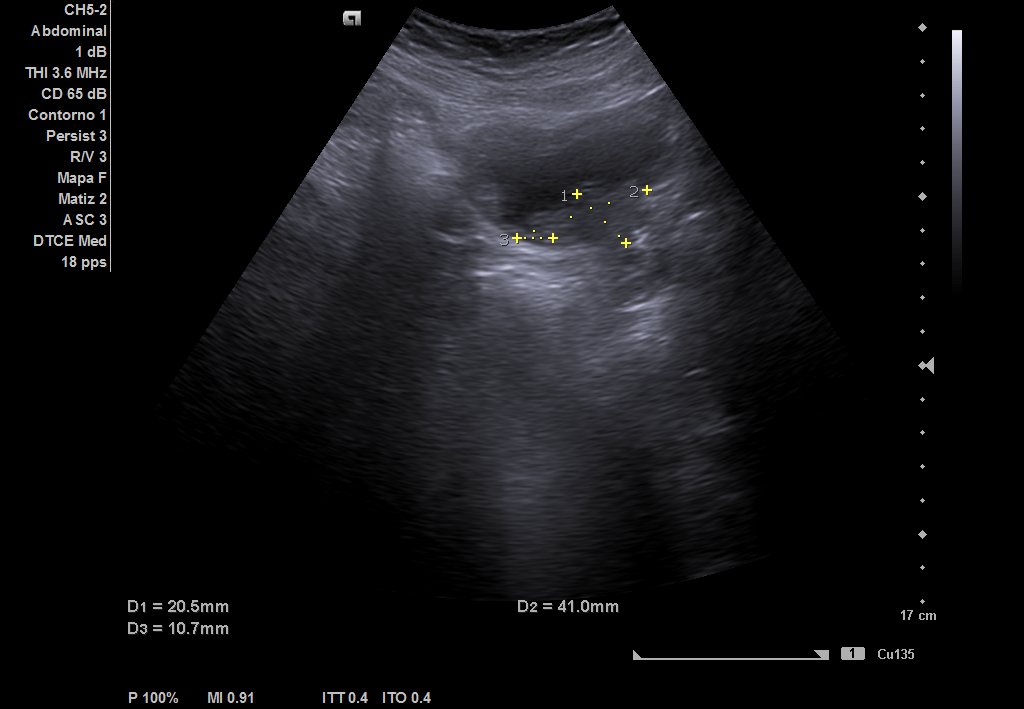

Ecografía urinaria: vejiga bien replecionada, observándose masa en trígono de 20 x 12 mm. Riñón derecho con dilatación pielocalicial moderada, sin hidronefrosis. Riñón izquierdo sin alteraciones reseñables.

Comparamos con informes previos de ecografías, objetivando cambios. Valorando la clínica (STUI y hematuria) y las imágenes, sospechamos de invasión tumoral uretral y crecimiento de tumor. Solicitamos analítica, observando empeoramiento renal con creatinina de 2.1 y FG 27.28.

Ecografía reglada: ureterohidronefrosis grado III secundaria a lesión en uréter medio-distal. Vejiga parcialmente replecionada con material ecogénico en suelo vesical con aparente doppler color e interior. Posible coágulo vs lesión subyacente.